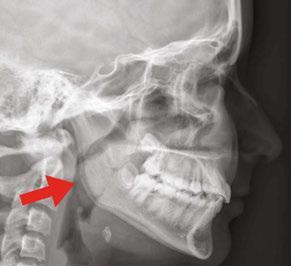

Drs. Claudia Pinter and Stanley Liu illustrate a protocol to improve nasal breathing in orthodontic care 31